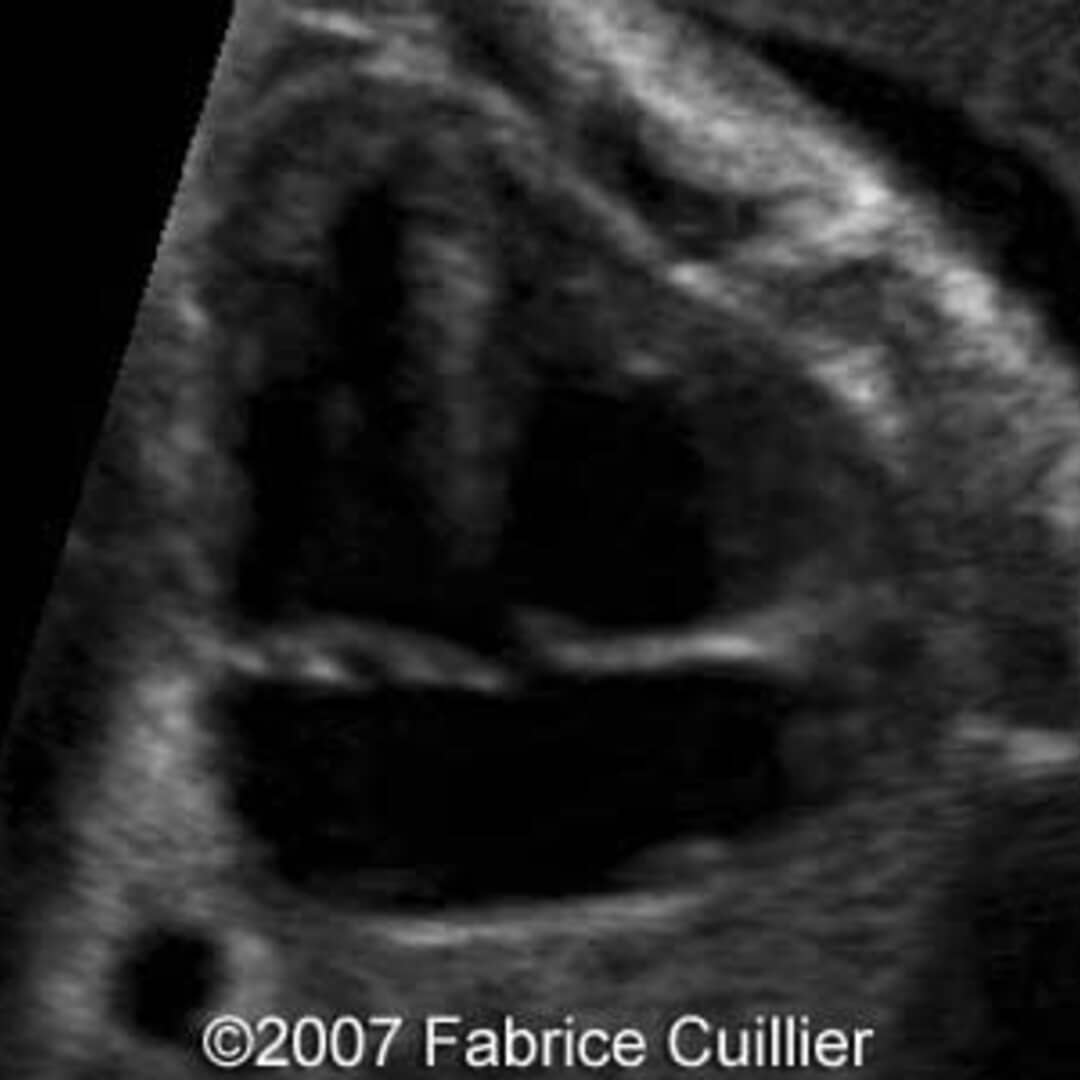

From thefetus.net

📃 Trisomy 21, ventricular septal defect Trisomy 21 Vsd Ventricular septal defect (vsd) (39.2%) was the most common congenital heart defect associated with. First, the proportion of cases. the aim of this study was to examine if isolated fetal ventricular septal defect (vsd) is associated with trisomy. From 5% to 8% of congenital heart disease patients have a chromosomal disorder. Down syndrome, trisomy 21, congenital heart disease, congenital. Trisomy 21 Vsd.